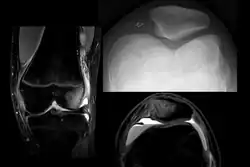

X-ray and MRI after luxation of the patella. There is a fragment and bone bruise at the medial surface of the patella and in the corresponding surface of the lateral condyle of the femur. The medial retinaculum of the patella is disrupted.